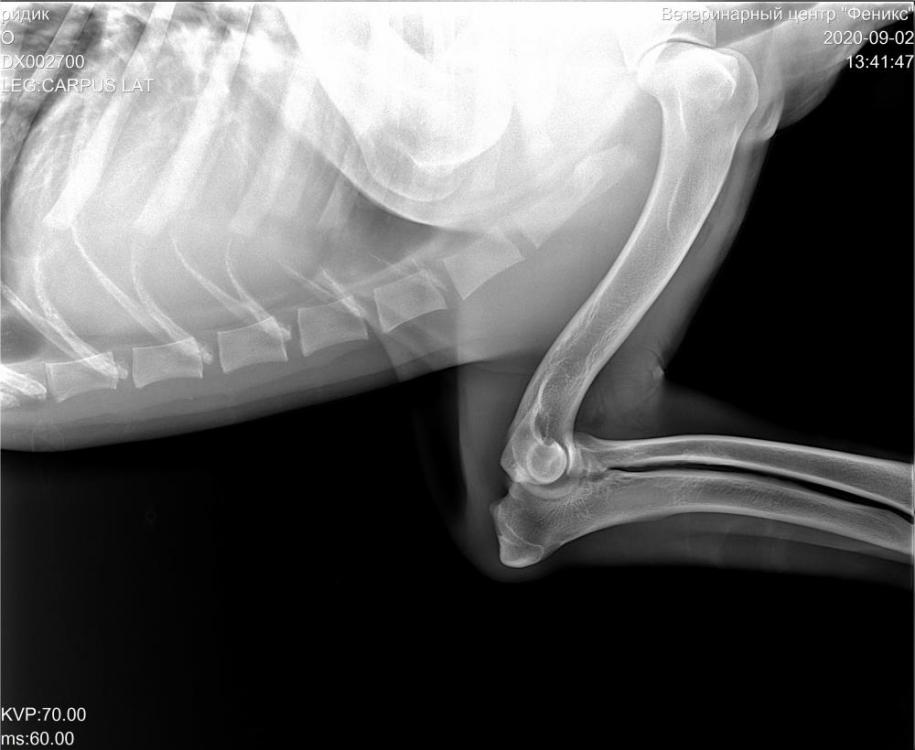

alkor17 Опубликовано 3 сентября, 2020 Автор Опубликовано 3 сентября, 2020 Вот такой у нас рентген. Проблема с левой передней лапой. Локтевой сустав как бы вывернут наружу. Но при этом он ходит, бегает, прыгает, никакого беспокойства не проявляет. Что это может быть? Будем проверять, пока есть возможность только отправить снимки на онлайн консультации, поехать с собакой в Москву возможности не будет в ближайшее время. 2